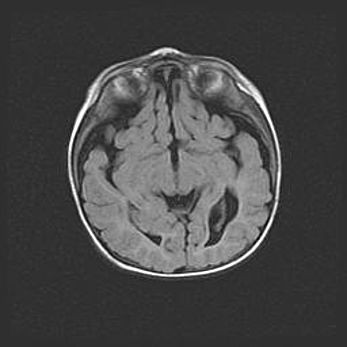

Множественные кисты обоих полушарий головного мозга, наибольшая из них в правой затылочной области. Ассиметричная атрофическая гидроцефалия.

Возраст: 7 месяцев

Вес: 5660 г

Пол: мужской

Окружность головы: 41,5 см

Срок гестации: 28-29 недель

Кисты головного мозга развиваются в результате многоочаговых некрозов вещества мозга и возникают вследствие перенесенной перинатальной инфекции, менингитов, энцефалитов, асфиксии, родовой травмы, расстройств мозгового кровообращения различного генеза. Образованию кист в веществе головного мозга плодов и новорожденных способствуют такие факторы, как высокое содержание в нем воды, недостаточная (или отсутствие) миелинизация и слабая астроглиальная реакция на повреждение.

Кисты могут сочетаться с гидроцефалией и другими поражениями головного мозга.